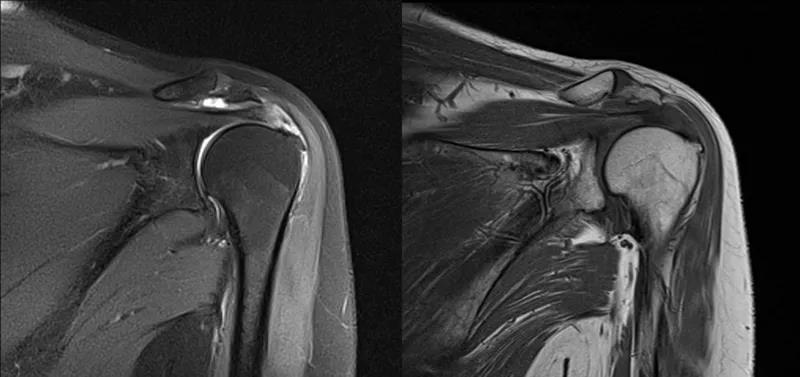

图21 斜冠状位(临床常用)a.T2,b.T1

图22 斜矢状位 a.冈上肌出口,肩袖诊断不如斜冠状位;b.冈上肌及肌腹脂肪浸润成度,评估手术与否